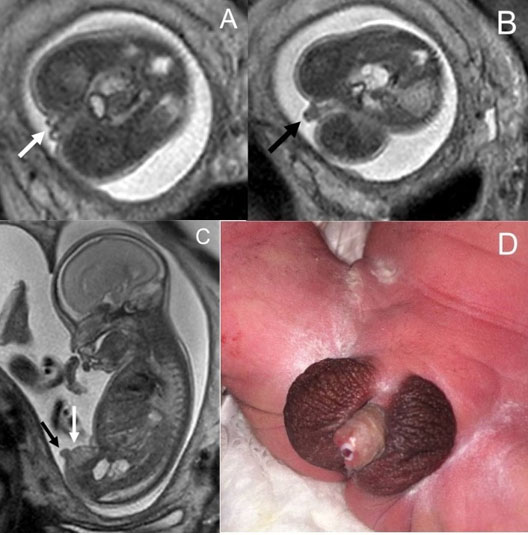

This was a male baby born to a 24-year-old mother G2P0010, referred to the CFCC for multiple fetal anomalies noted on US. Early fetal US showed small, ambiguous genitalia and cystic left pelvic kidney. Fetal MRI findings showed abnormal external genitalia with inverted position of the scrotum and phallus, not ambiguous genitalia. Flattened or squared-off termination of the phallus suggesting hypospadias was also noted. There was abnormal abrupt termination of the meconium column on T1-weighted fetal MRI images at the level of the distal descending colon with absent anal dimple, suggesting imperforated anus. Additional syndromic features/anomalies on fetal MRI included a multicystic dysplastic left kidney and normal right kidney (Figure 2).

Figure 2: Axial (A and B) and sagittal (C) Single Shot Fast Spin Echo MR images of a 25 weeks 3 days male fetus showing bifid appearance of the scrotum (white arrows in A and C) and a foreshortened and squared off phallus located inferior to the scrotal sacs (black arrows in B and C). Photograph of the same patient’s genitalia at day of life 2 (D).

Figure 3: Axial (A), coronal (B), and sagittal Single Shot Fast Spin Echo (C) MR images of a 27 weeks 6 days female fetus with ambiguous genitalia. See the prominent clitoris (white arrows in all images), prominent labia majora (black arrows in A and B). On the sagittal view, the appearance is similar to our patient in case 3, male sex and penoscrotal transposition. But in this case, the uterus was seen posterior to the bladder and anterior to the rectum in axial plane MRI (open white arrow in A). Gray scale transverse plane (D) and 3D volume rendering US (E) show the same findings.